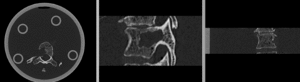

this is the fixed reference image. All images are aligned into this space lleft this is the moving image. The transform is calculated by matching this to the reference image

fixed image/target moving image

We have 2 in vitro CT scans of a human thoracic spine, before and after application of a controlled structural damage. We apply a rigid registration to bring the two images into alignment. Because the container tube and fixtures add image content that is "distracting" to the registration, we crop both images to contain just the vertebra of interest. Also the spines were not imaged in the same orientation, and as consequence we have an inverted z-axis in one of the images we have to correct first. Finally the two images have very different spatial origins (as defined in original DICOM header), so we need to recenter first before running the registration.

Registration Results

RegLib C39 unregistered.gif before registration (click to enlarge)